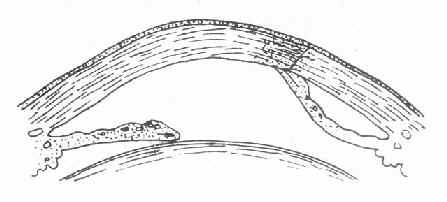

(二)进行期 如浸润阶段的炎症没有得到控制,浸润将蔓延扩大,随后新生血管将伸入浸润区,特别是周边部的炎症更是如此。在浸润区嗜中性白细胞溶解,释放出含有水解酶的溶酶体颗粒。水解酶与角膜蛋白发生反应,导致浸润区的角膜上皮层,前弹力层和基质层坏死脱落,角膜组织出现缺损,形成角膜溃疡(corneal ulcer),又称溃疡性角膜炎(ulcerativekeratitis),溃疡边缘呈灰暗色或灰黄色混浊。如溃疡向纵深发展,即形成深层溃疡,溃疡底部不平。由于毒素的刺激可并发虹膜睫状体炎;严重时,大量纤维蛋白性渗出物集聚于前房下部形成前房积脓(hypopyon)。当角膜基质完全被破坏、溃疡波及到后弹力层时,由于局部抵抗力降低,眼内压力可使后弹力层及内皮层向前膨出,称后弹力层膨出(descemetocele)。临床检查时在溃疡底部可见“黑色”透明小泡状突起。这是角膜即将穿孔的征兆。此时,若眼球受压,例如揉眼、碰撞、打喷嚏、用力咳嗽、便秘等,均可造成角膜骤然穿孔。在穿孔瞬间,病人可自觉眼部突然剧疼,并有热泪(即房水)流出。穿孔后可引起一系列的并发症和后遗症。

(三)恢复期即炎症的转归阶段。经过治疗,溃疡可逐渐转向清洁,周围健康角膜上皮细胞迅速生长,将溃疡面完全覆盖,在角膜上皮细胞的掩盖下,角膜基质的成纤维细胞增生和合成的新胶原,修补基质的缺损处,角膜溃疡遂告痊愈。角膜中央区溃疡愈合方式多为无新生血管性愈合;周边部溃疡多为有血管愈合。新形成的角膜基质胶原纤维排列紊乱,构成了不透明的瘢痕组织。位于中央区的致密瘢痕可使患眼视力严重丧失。浅层溃疡,仅有角膜上皮层覆盖创面,无结缔组织增生者,则在损伤处形成透明的小凹面,荧光素不染色,称为角膜小面(corneal facet)。(图6-1,6-2)

1、上皮脱落 2.溃疡及前房积脓 3.后弹力层膨出

图6-1 角膜溃疡

图6-2 角膜溃疡进行性演变